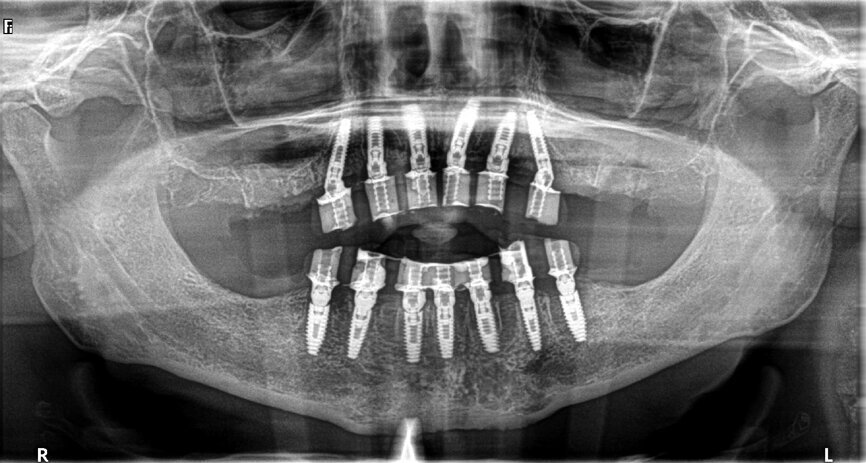

Fig. 20: Post-op panoramic view.

A CBCT scan and panoramic radiograph using the CS 8100 3D (Carestream Dental; Figs. 4 & 5) was taken to accurately capture the information needed to properly plan treatment for this case to ensure the most ideal outcome, especially since the patient had discussed his frustration with previous treatment that did not last very long or address his primary needs or requests. Using CS 3D Imaging Software (Carestream Dental), dental implants were virtually planned in key positions in both arches (Fig. 6).

Seven days postoperatively, the patient returned with very little discomfort, swelling and bruising. He was very pleased with his new maxillary and mandibular fixed provisional restorations (Figs. 19 & 20). With the patient no longer anaesthetised, the occlusion was checked again to confirm there were no interferences in lateral and protrusive movements. The next step in his treatment would consist of full-arch impressions for the definitive restorations approximately four to five months postoperatively.